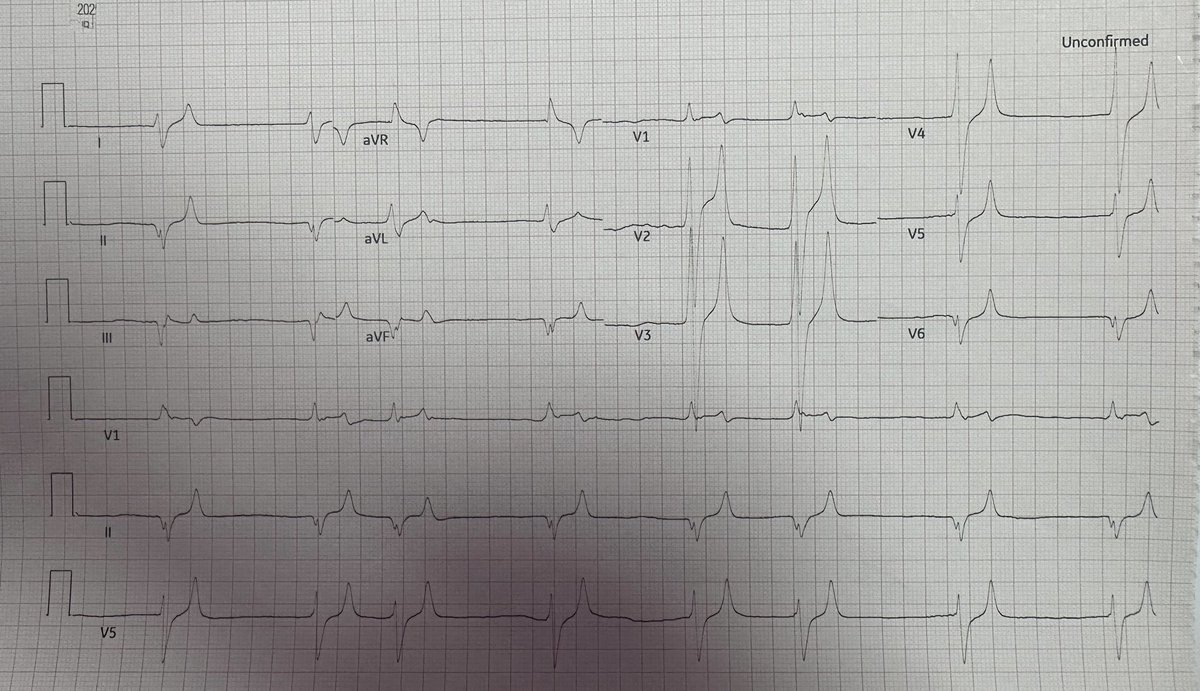

Chest pain and nausea with a diagnostic ECG drsmithsecgblog.com/chest-pain-and… Pendell Meyers